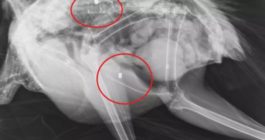

Το παγώνι φέρεται να δέχθηκε πυροβολισμούς, γεγονός που επιβεβαίωσαν και σχετικές ακτινογραφίες που «έδειξαν» μάλιστα δυο βολίδες αεροβόλου κι ένα σκάγι.

«Το ζώο αυτό έχει πυροβοληθεί τρεις φορές, την ίδια ώρα ή διαφορετικές δεν μπορούμε να ξέρουμε, ούτε αν ο δράστης είναι ένας ή δύο ή τρεις, μέσα ή δίπλα σ’ έναν από τους πιο πολυσύχναστους αρχαιολογικούς χώρους της Κρήτης και της Ελλάδας γενικότερα» αναφέρει χαρακτηριστικά σε ανάρτηση του ο Σύλλογος ΑΝΙΜΑ.